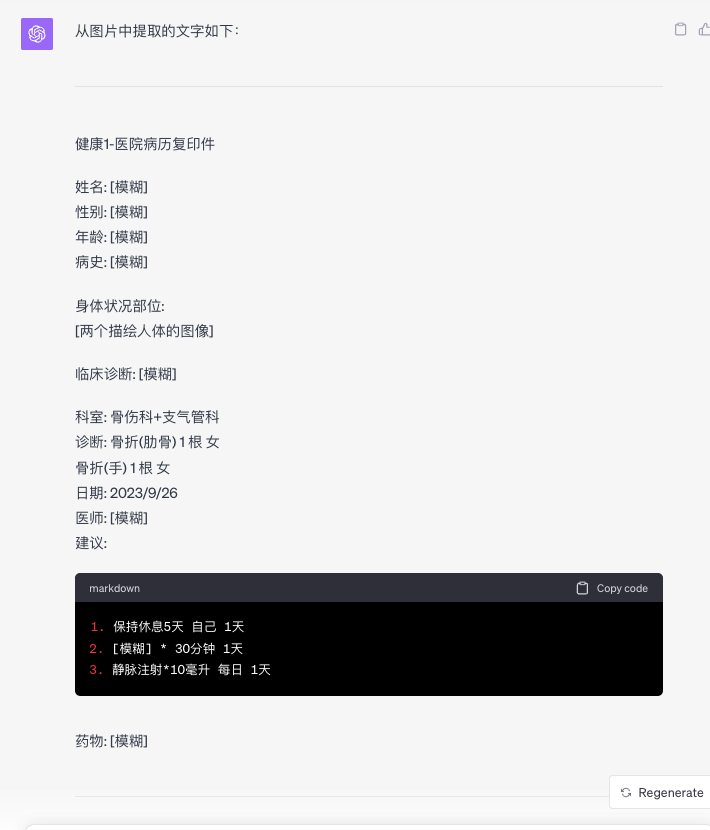

中文:电脑截图(准确)

中文:清晰中文表格图片(幻觉严重)

中文:有复杂信息的真实患者诊疗单(幻觉严重)

患者诊疗单(给GPT的是原图,以下图片经过二次处理模糊了患者信息)

1.1 OCR功能(幻觉严重,中文效果差)

有精确性要求的文字工作:如1.1节 患者诊疗单等OCR场景。

ChatGPT Vision试图以大模型的涌现能力,从高层次理解整个图片,将图片如同文字一般对待,而非是OCR式的匹配识别。ChatGPT Vision和OCR的区别,与语义搜索和关键词搜索的区别类似。